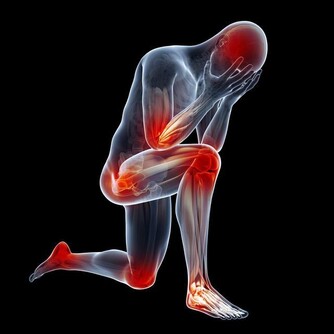

腳部是身體的最末端,即也是血液循環的最末端,如果腳部出現血液滯留將會影響整個身體的供血工作。血液循環不暢通,將會導致身體的新陳代謝速度減慢,受到影響最大就是消化系統和神經系統。

消化系統的工作進程減慢,將會導致脾胃失調,胃功能下降,胃部急劇過多的食物,無法及時消化繼而影響身體吸收足夠的養分來維持生命體活動。

神經系統則主要表現為,腦部疲勞,經常感覺到力不從心。久而久之將會導致記憶力下降,年輕人還會出現智力下降的現象。